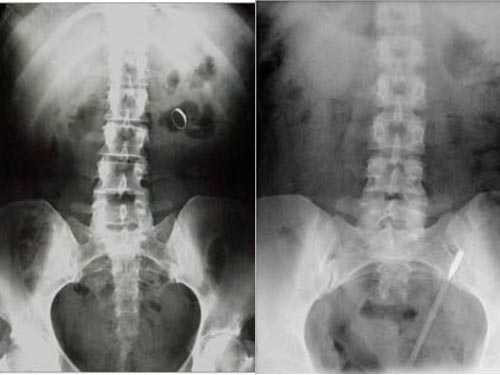

![]() |

| Nhẫn đính hôn và nhiệt kế mắc trong cơ thể bệnh nhân |